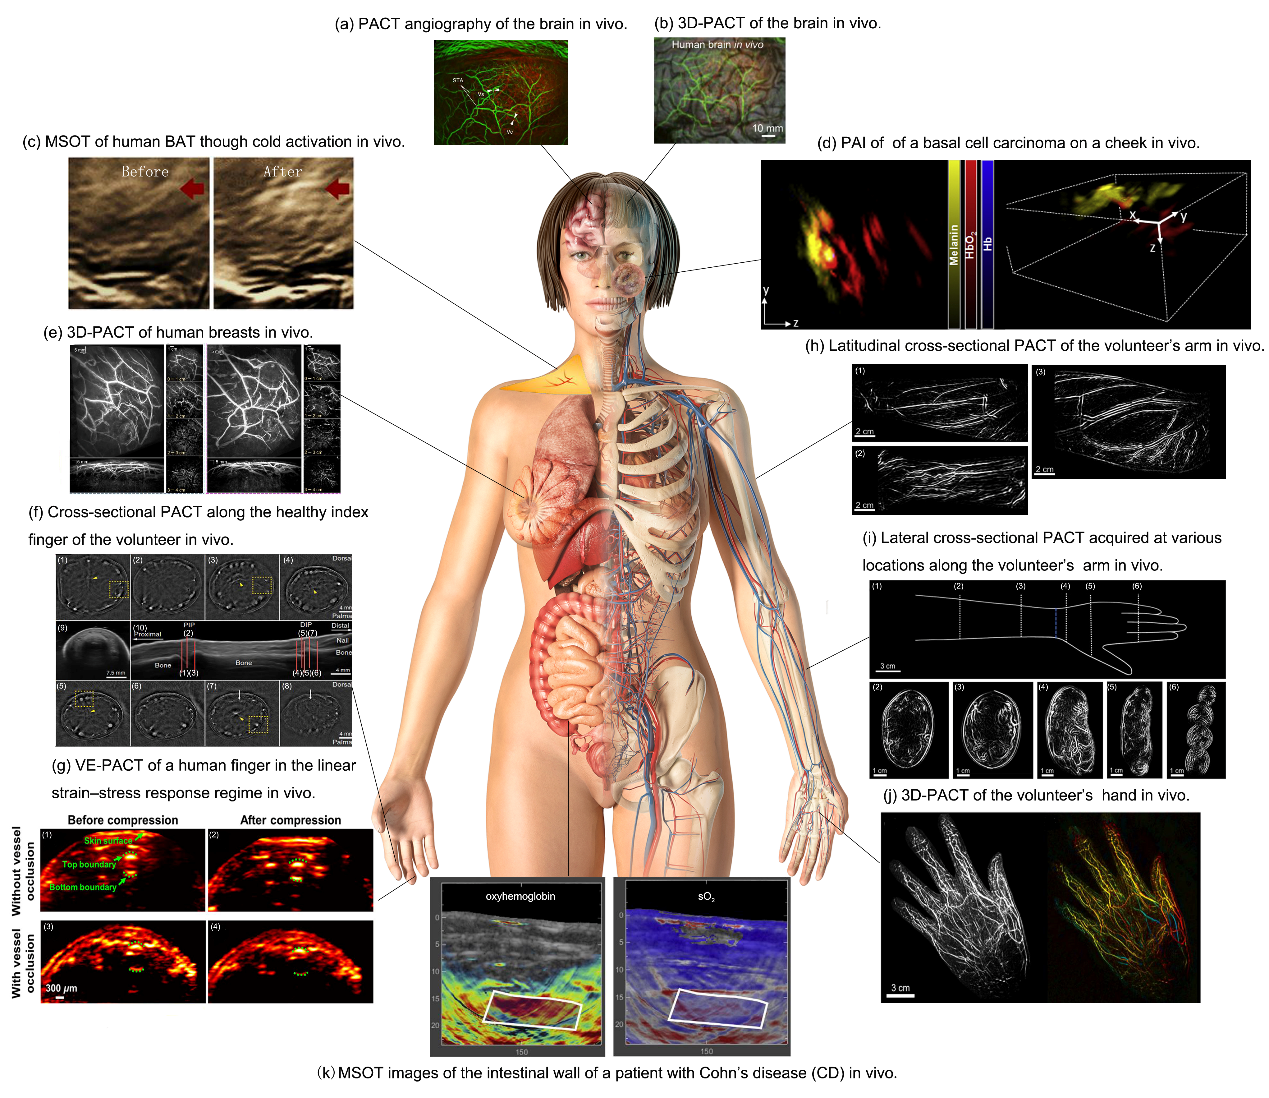

图2人体PACT成像

最近,PACT在临床前和临床实践中受到越来越多的关注。到目前为止,已经出现了越来越多为特定的生物医学成像应用而设计的PACT系统,实现了从小动物(图1)到人体器官(图2),从体外到体内实时成像,从简单的结构成像到使用外部造影剂的功能和分子成像。因此,总结以往PACT系统在生物医学成像和临床实践中的应用是非常重要的。这篇综述中搜索了过去二十年来与生物医学组织和样本的PACT成像有关的研究;将这些研究分为两类,即动物的PACT成像和人类组织、器官的PACT成像,并讨论了这些研究的意义。最后讨论了PACT在生物医学应用中的未来方向。随着外源性造影剂的发展和成像技术的进步,未来PACT将使生物医学成像从器官到全身,从表层血管到内部器官,从解剖到功能,在生物医学研究和临床实践中发挥越来越重要的作用。